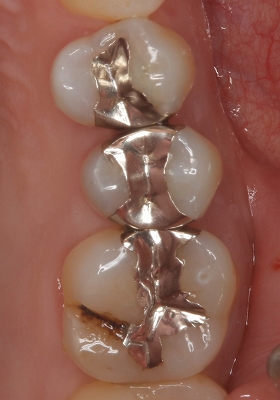

口腔内写真

2026 EEdental NNS (2).jpg

低目にレジンが詰めてあります。

患者さんには咬頭が無くなっており、中で虫歯もひろがっていそうだから

メタルアンレーで治しましょうと説明

治療を開始すると、「え!?」というぐらい詰め物が深い

歯茎の中のレジンも途中までしか詰めれておらず隙間から歯の中に歯茎が入り込んで来ている・・・

途中からこれ初発は虫歯ではなく歯冠破折で、長い期間で隙間から2次カリエスが出来たケースだと分かってきました。

歯の中の歯茎は電メスを使い除去

虫歯を削り終わると

2026 EEdental NNS (3).jpg

露髄した部分には第3象牙質が見られます。

エナメル質をなるべく残す為にEENOスフィアなどを使いくり抜くように虫歯を削っています。

ただ、こうなるとメタル修復するよりレジンで治した方が良いと判断し

患者さんとお母さんに理由を説明してレジン充填を行いました。

術前⇒術後

2026 EEdental NNS (5).jpg

レントゲン

2026 EEdental NNS (4).jpg

最後に咬合をチェックすると臼歯部に側方運動時のガイドがあり、

たぶん、昔もこのガイドが極端に強くて割れたんだろうなと推測。

2026 EEdental NNS (6).jpg

*最初の図と同じ割れ方になってました。

遠心にも似たようなガイドがあったので、最後に側方運動の咬合調整を行い終了となりました。